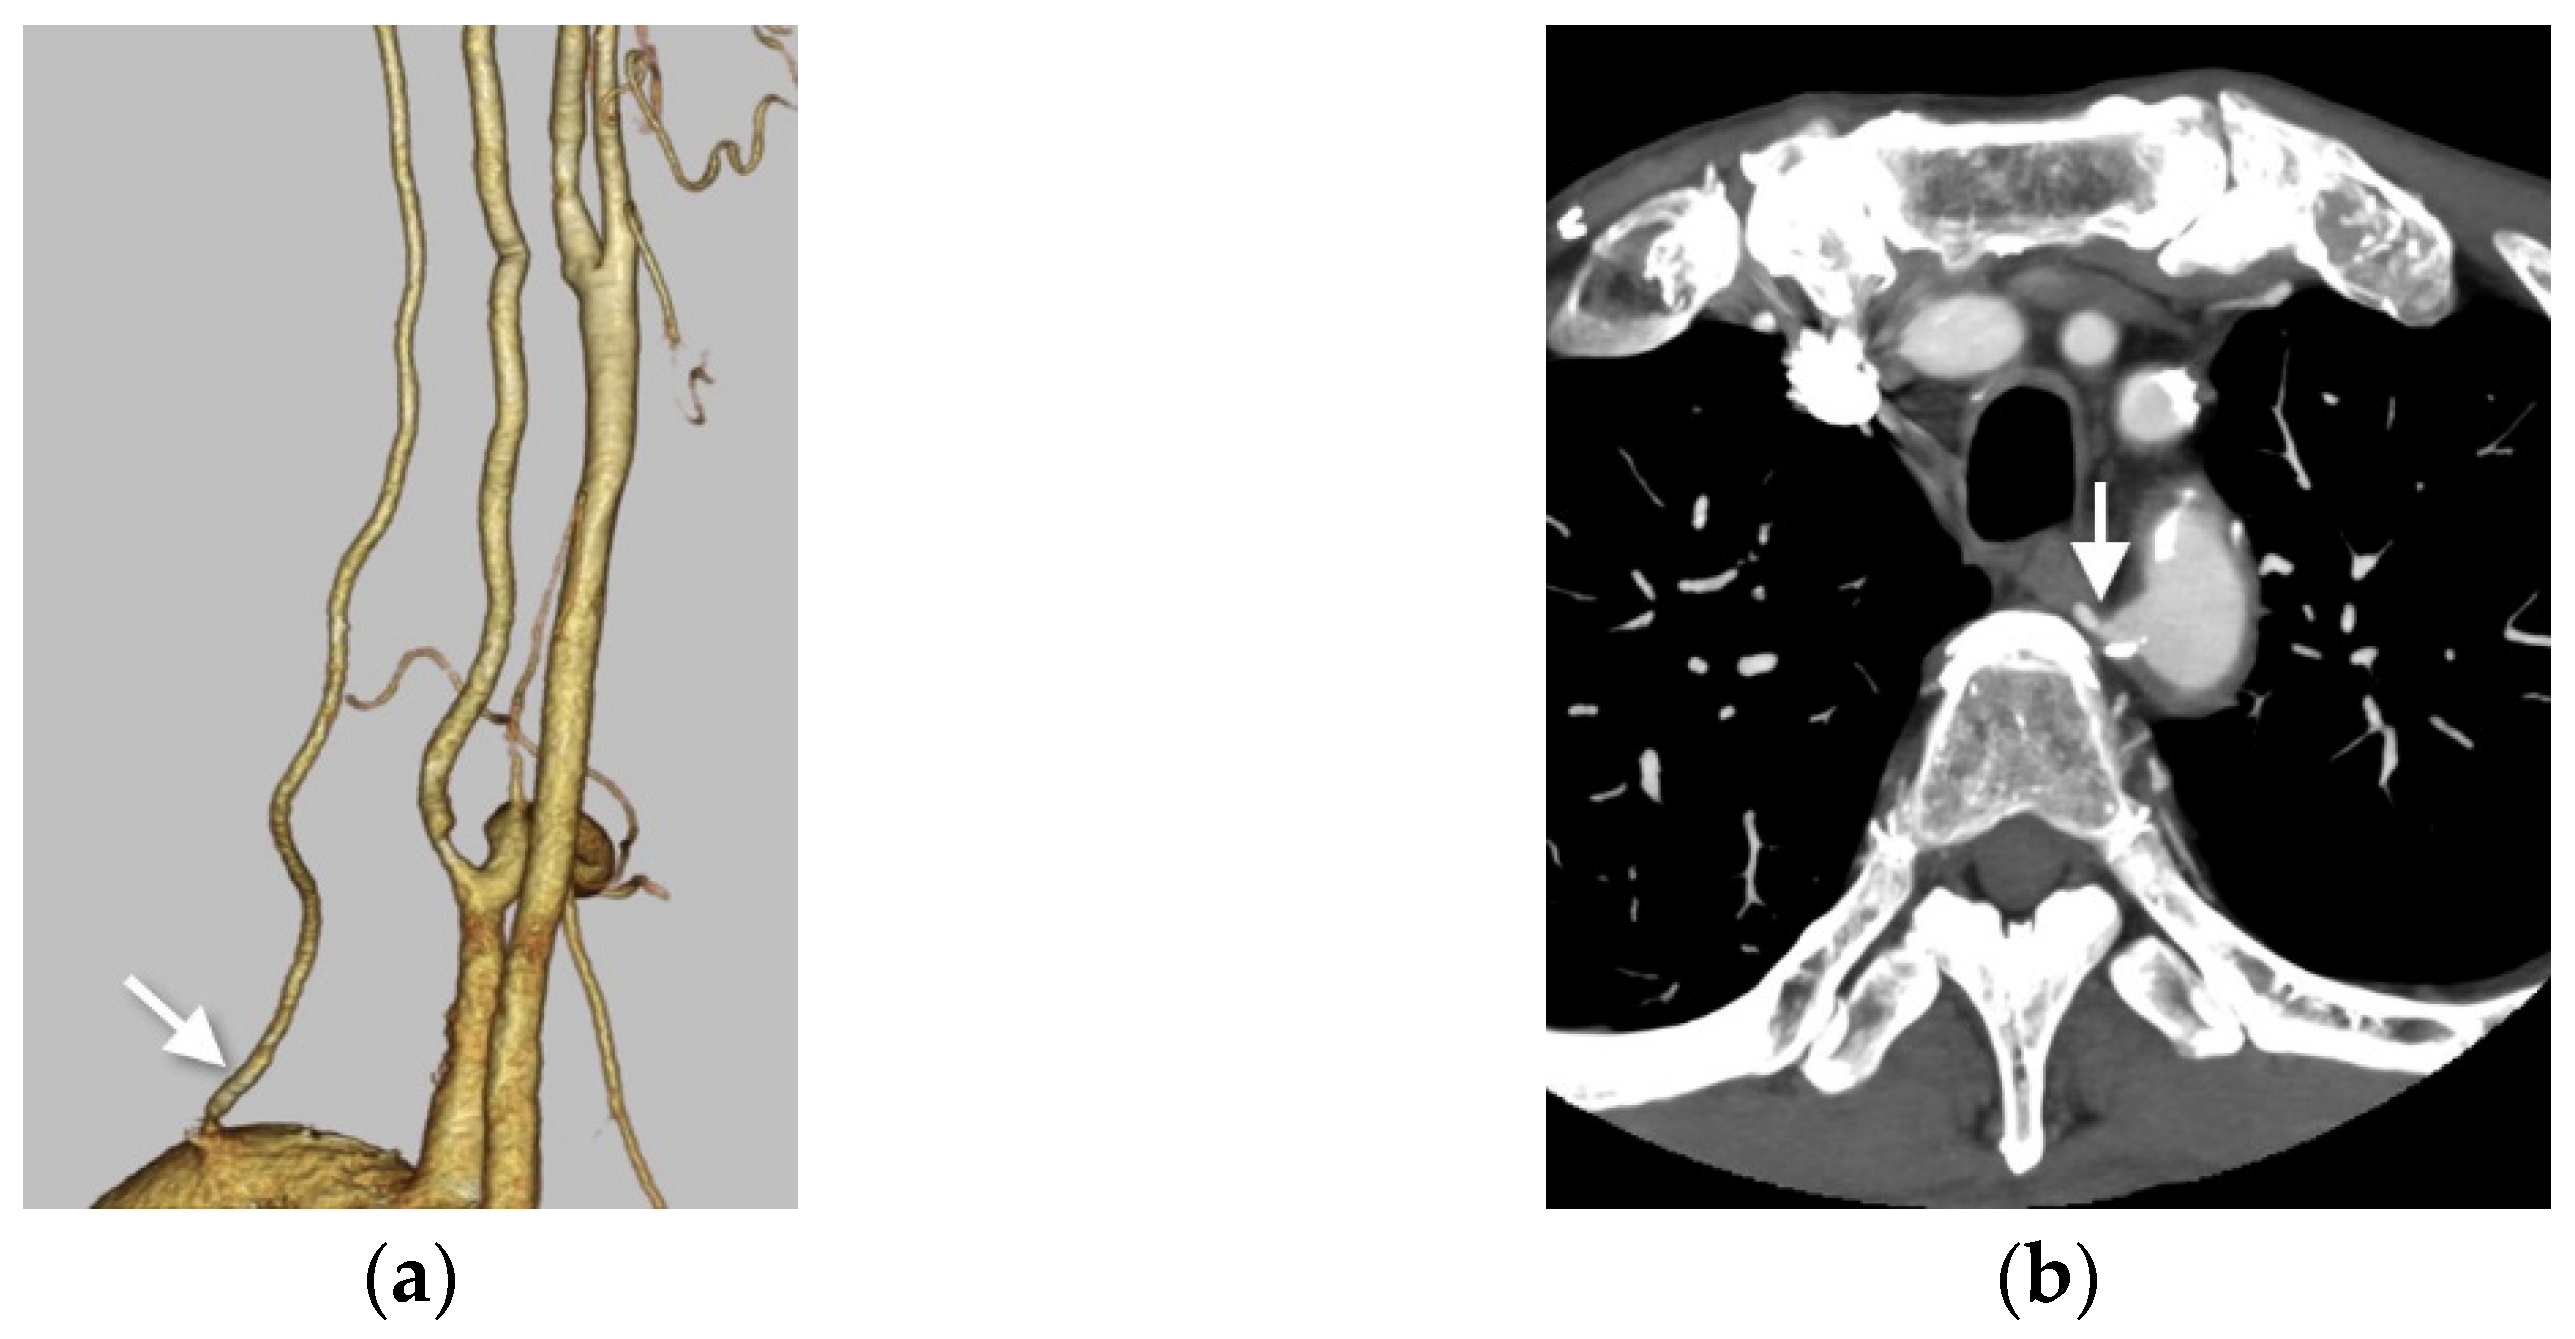

3.1. Right VA Originating from the Aortic Arch (Aortic Origin)